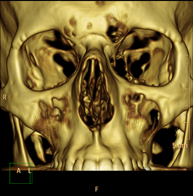

- Facial mass CT

Radiological test that provides high definition anatomical images of the facial mass (face) using CT (Computed Tomography) equipment. Indicated for: tumours, plastic surgery.

- Paranasal Sinuses CT

Radiological test that provides high definition anatomical images of the paranasal sinuses using CT (Computed Tomography) equipment. Indicated for: headache, mucus, facial infections.